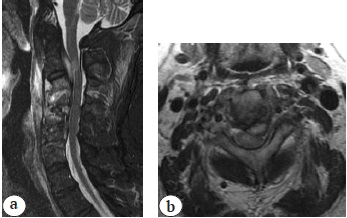

Early postoperative period was complicated by the development of deep SSI, for which empiric antibacterial treatment (parenteral injection of vancomycin 1.0 twice a day for 3 weeks) was administered. Revision surgeries (necrectomy, abscessotomy, removal of interbody cages) were not performed. Cervical spine MRI in the setting of deep SSI (16 days after anterior cervical discectomy and C4-C5 spondylodesis) showed the presence of an epidural abscess and focal myelopathy at the C2-C3 level, a prevertebral abscess at the C2-C6 level and spondylitis at the C3-C5 level (Fig. 3).

Fig. 3. MRI after the second operation: a — STIR images; b — T2 images: prevertebral, epidural abscesses, C3–С5 spondylitis, focal myelopathy at C2–С3